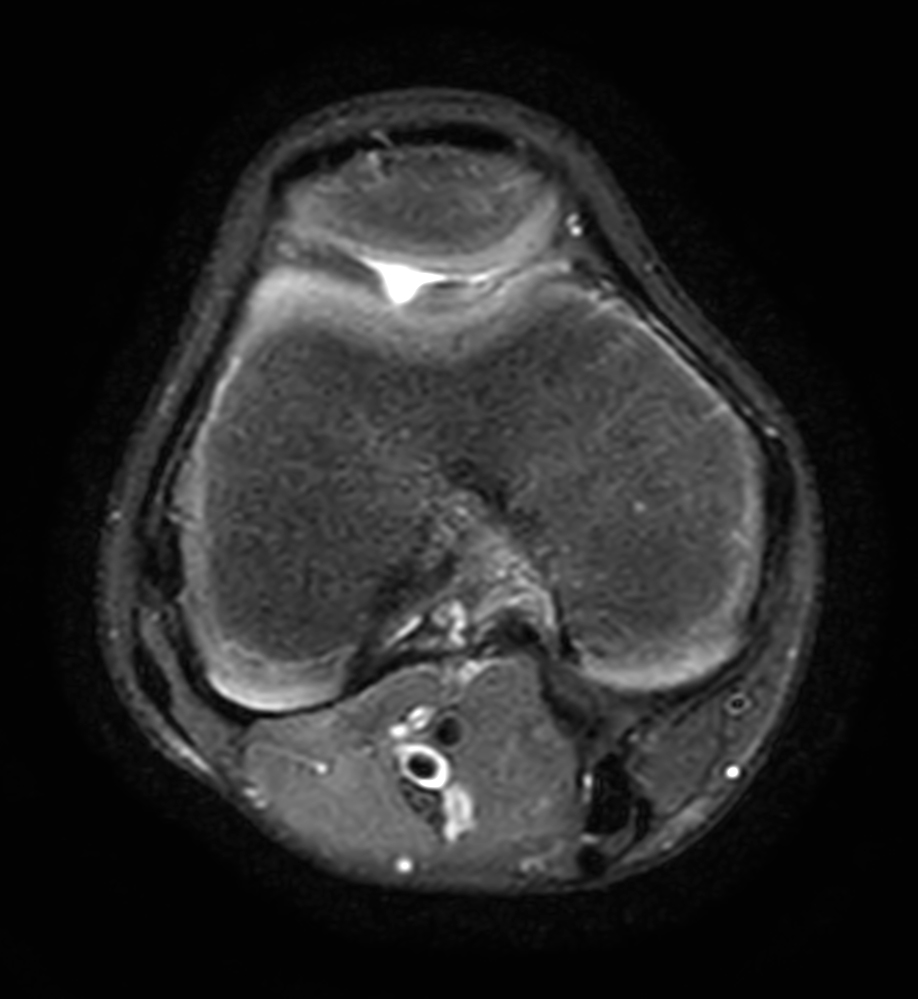

3D VIEW PDw SPAIR - Axial reformat

Axial T2w SPAIR